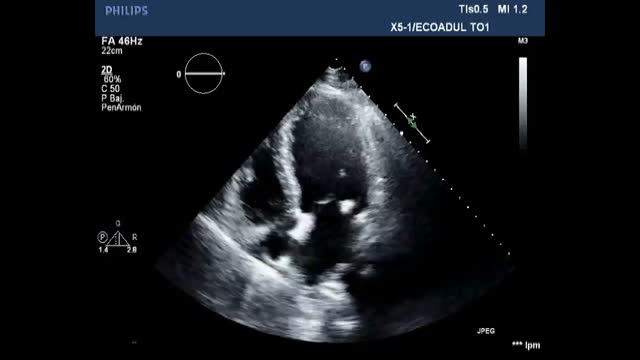

Pericardial tamponadeLeads to right ventricle collapse and decrease of RV output and by consequence LV output. From a subcostal view, we can assess the presence of pericardial effusion, which compromises the functionality of the heart. In a basic analysis of shock, the existence of severe effusion (>2 cm), collapse of the cavities in their respective diastoles, dilation of the Inferior Vena Cava with absence of respiratory variations and in some situations, visualisation on the two-dimensional TTE of “Swinging heart” which is associated to a large pericardial effusion testifies often cardiac tamponade.17

Pulmonary embolismTTE can help to establish a prompt diagnosis of acute pulmonary embolism (PE) and to identify patients with high-risk features. Additionally, when the patient is hemodynamically unstable, TTE may be the only immediately available and appropriate imaging investigation. 19

Using a basic approach, the cause of the shock towards PE when we observe the evidence of hyperechogenic images in the right cavities, in this context, has a high specificity of PE. Additionally, signs of the consequences of acutely increased pulmonary artery/right heart pressures can be observed including dilatation of right heart chambers and more precisely the evolution of an initial abnormal ratio of RV diameter or area to LV diameter or area (Fig. 4, Video 3).